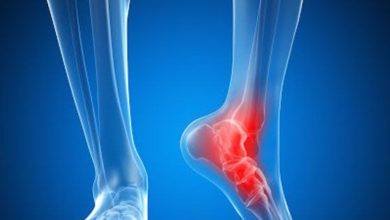

أكمل القراءة » - صحة العظام والمفاصل

أسباب الشوكة العظمية بالقدم وعلاجها بالأعشاب والطرق الطبيعية

الشوكة العظمية أو نتوءات الكعب هي تراكم الكالسيوم في الجزء السفلي من عظم الكعب، مسببًا آلامًا مبرحة مثل طعنة سكين…

أسباب ألم كعب القدم وطرق الوقاية

غالبًا تبدأ معاناة الأشخاص من الشعور بألم كعب القدم عند الاستيقاظ مع البدء في المشي أو عند الوقوف مدة طويلة،…

أكمل القراءة » - صحة العظام والمفاصل

علاج التهاب وتر العرقوب في المنزل

تعد مشكلات الأوتار المزمنة مصدرًا متكررًا للألم، وقد تتسبب في إعاقة نمط الحياة اليومي، عادة تزداد مشكلات الأوتار مع التقدم…